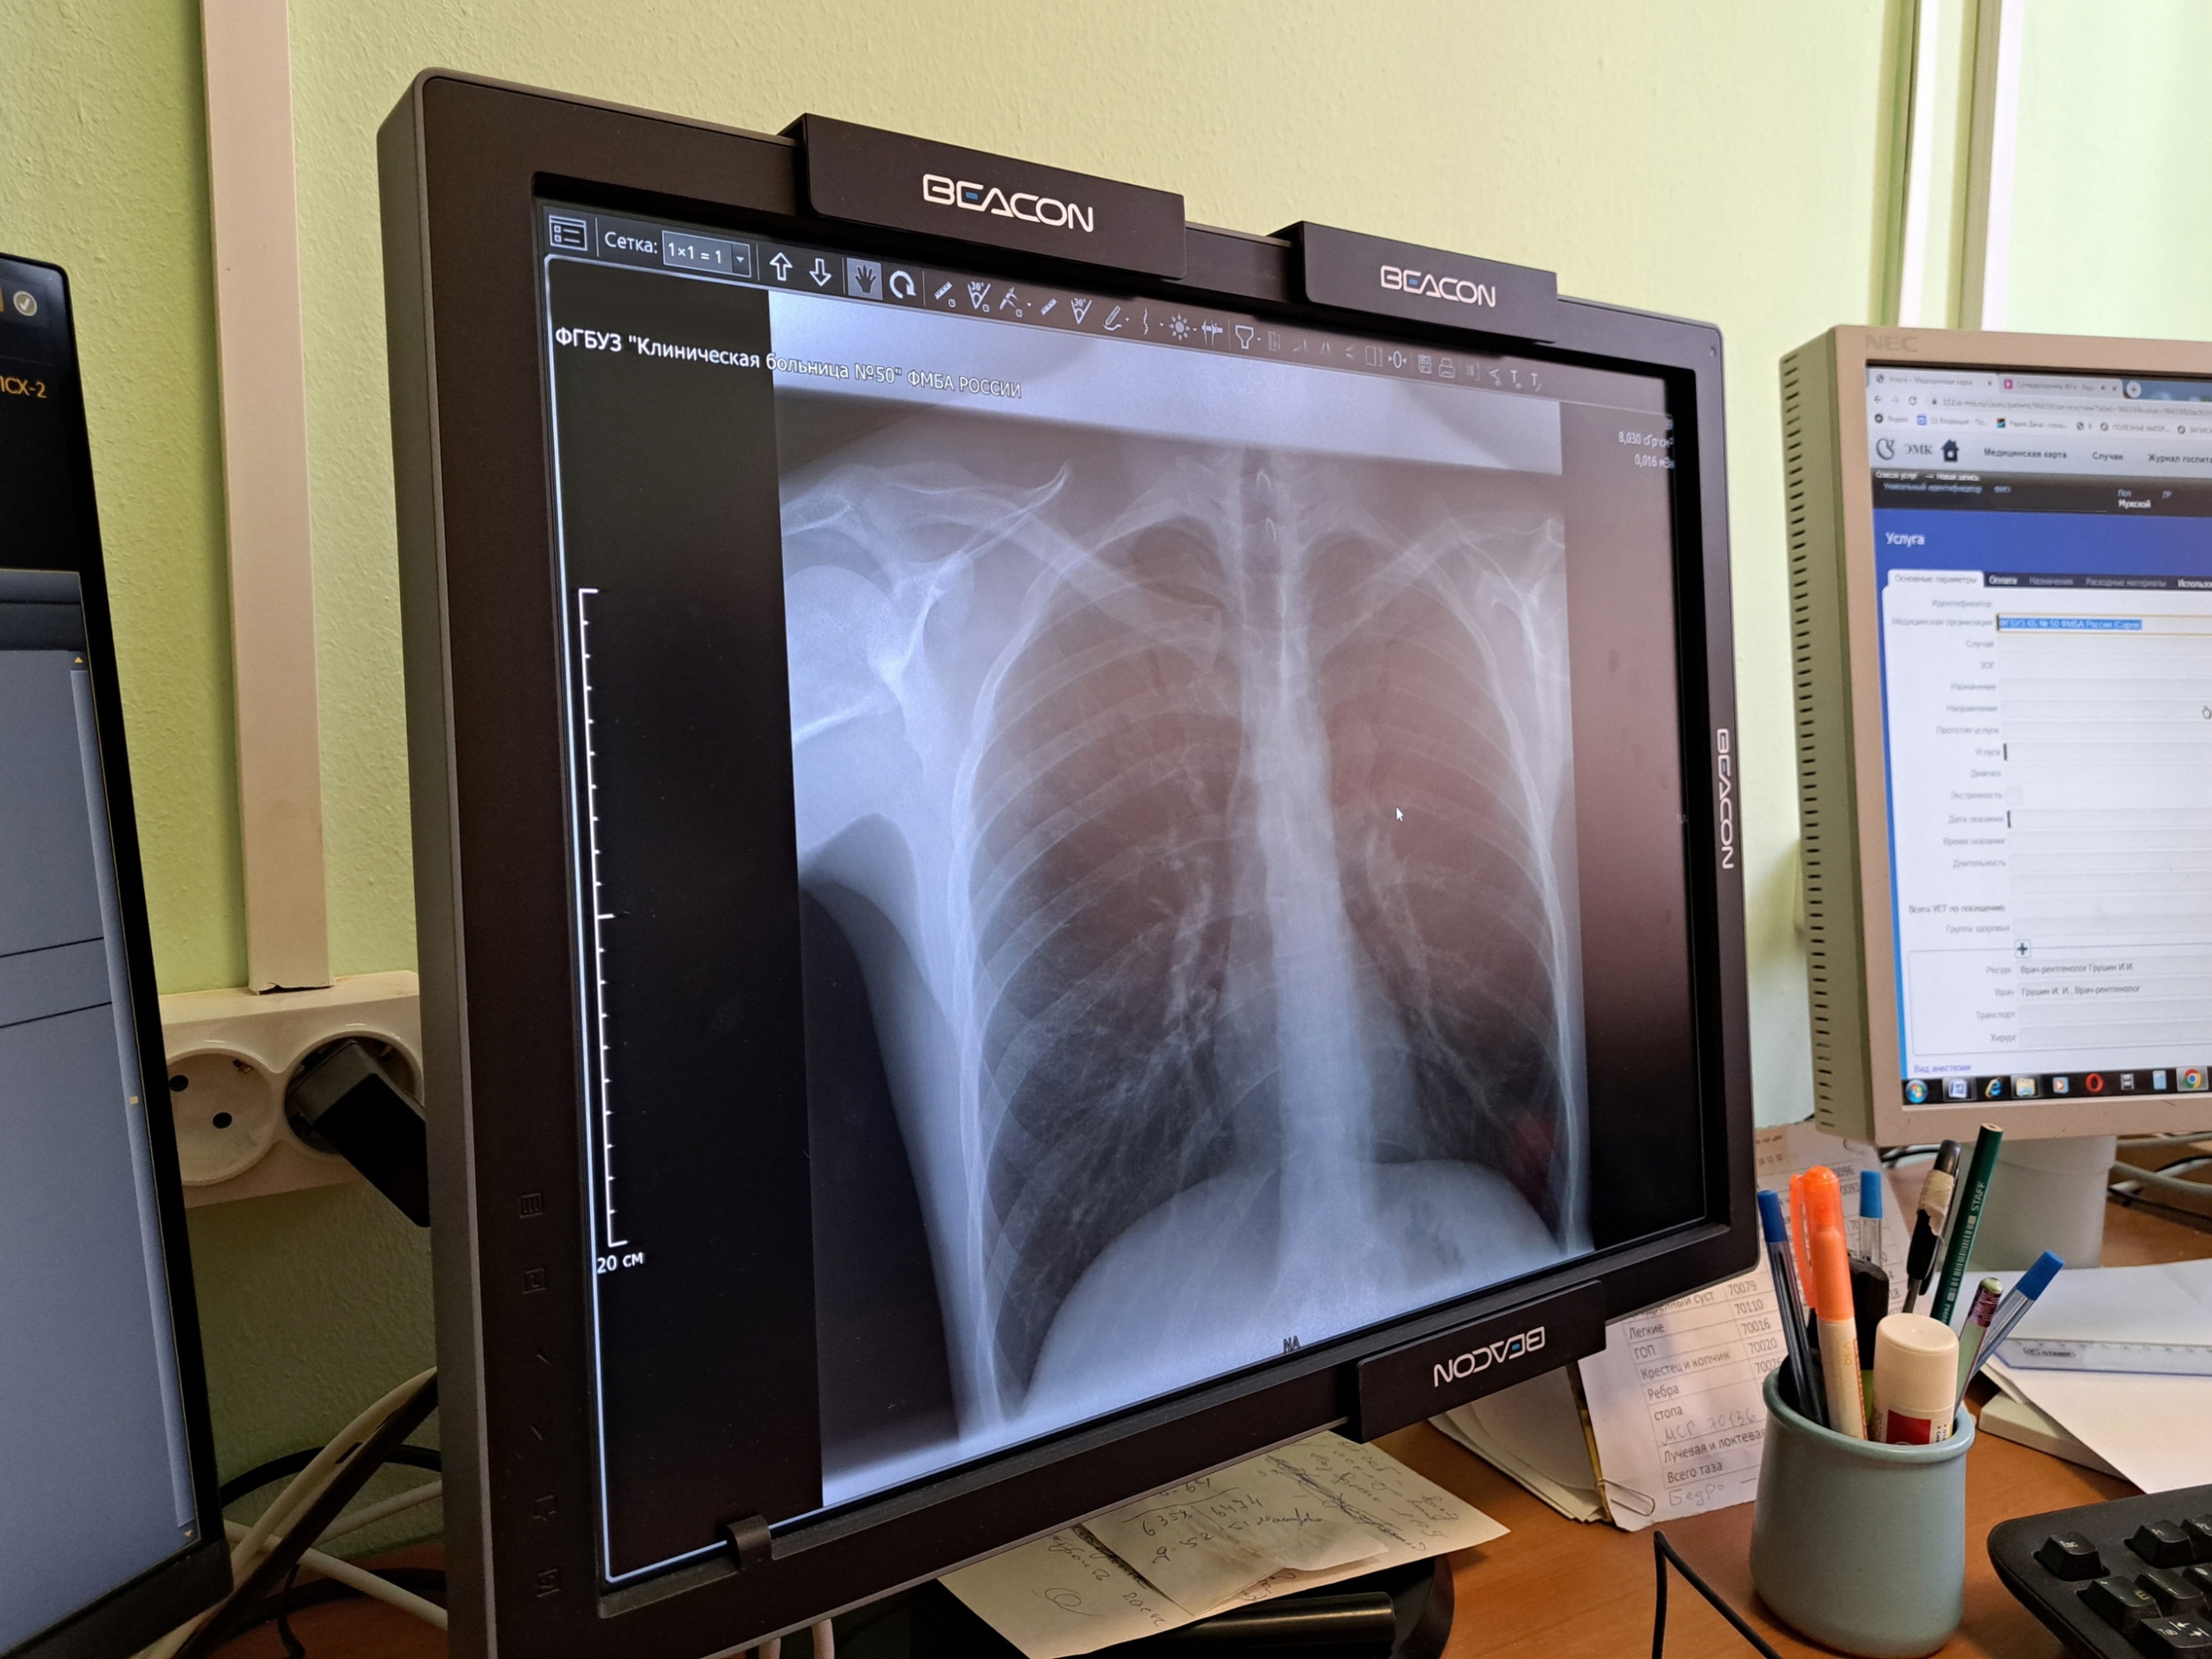

Недавно в распоряжение КБ-50 поступил современный цифровой рентгенодиагностический комплекс на три рабочих места. «Он позволяет проводить рентгенографию и рентгеноскопию. Мы можем диагностировать заболевания органов грудной клетки и брюшной полости, суставов, костей, позвоночника. Сама процедура проходит намного быстрее, чем на старом, пленочном оборудовании и занимает в среднем 5 минут, что удобно как для лаборанта, так и для врача. Если раньше мы делали снимок, затем его проявляли и только потом приступали к описанию, то сейчас вся информация сразу передается на компьютер», — рассказал врач-рентгенолог Иван Грушин.

«Снимки получаются очень высокого качества. Я могу подстроить под себя яркость и контрастность, рассмотреть мелкие детали. Аппарат оснащен современным программным обеспечением, которое помогает быстро и точно проводить диагностику, вести протоколы исследований. Снимки сохраняются в электронном виде в информационной системе и врач, который направил к нам пациента, может сразу увидеть результаты. При необходимости есть возможность записать их на диск», — рассказал врач-рентгенолог Иван Грушин.